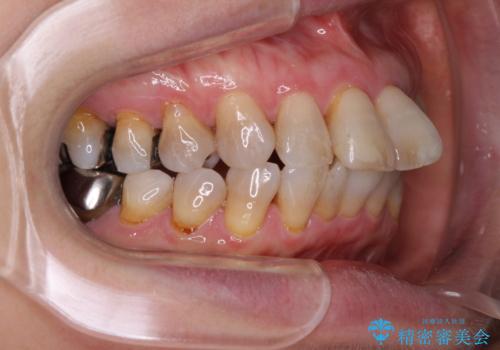

- 突出した口元を引っ込めることを希望して来院された患者様です。

上下左右第一小臼歯4本を抜歯して、口元を改善するワイヤー矯正を行うこととしました。

長年気にされていた口元の突出感が改善されたため、もっと若い時分に矯正をすればよかったと思われていました。